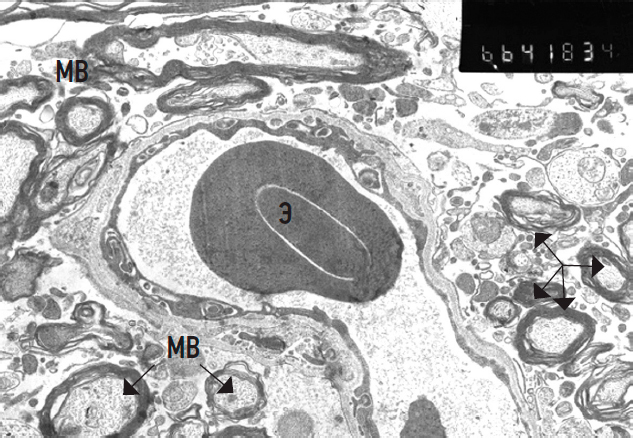

In the control group, the capillaries of the lumbar spinal microcirculatory bed had intact basal membranes. However, erythrocyte aggregation into rouleaux was observed in the vessel lumina, indicating erythrostasis.

Endothelial cells exhibited dystrophic changes, more frequently of the dark-type than pale-type. Astrocytic end-feet were often absent around the capillaries, with numerous adjacent myelinated fibers showing signs of myelinopathy and axonopathy (Fig. 10). These vascular and perivascular changes reflect moderate microcirculatory impairments.

Fig. 10. Capillary with erythrocytes (Э) in the lumen. MB — myelin fibers (arrows), ×6,600.

Рис. 10. Капилляр с эритроцитами (Э) в просвете. МВ — миелиновые волокна (стрелки), ×6 600.